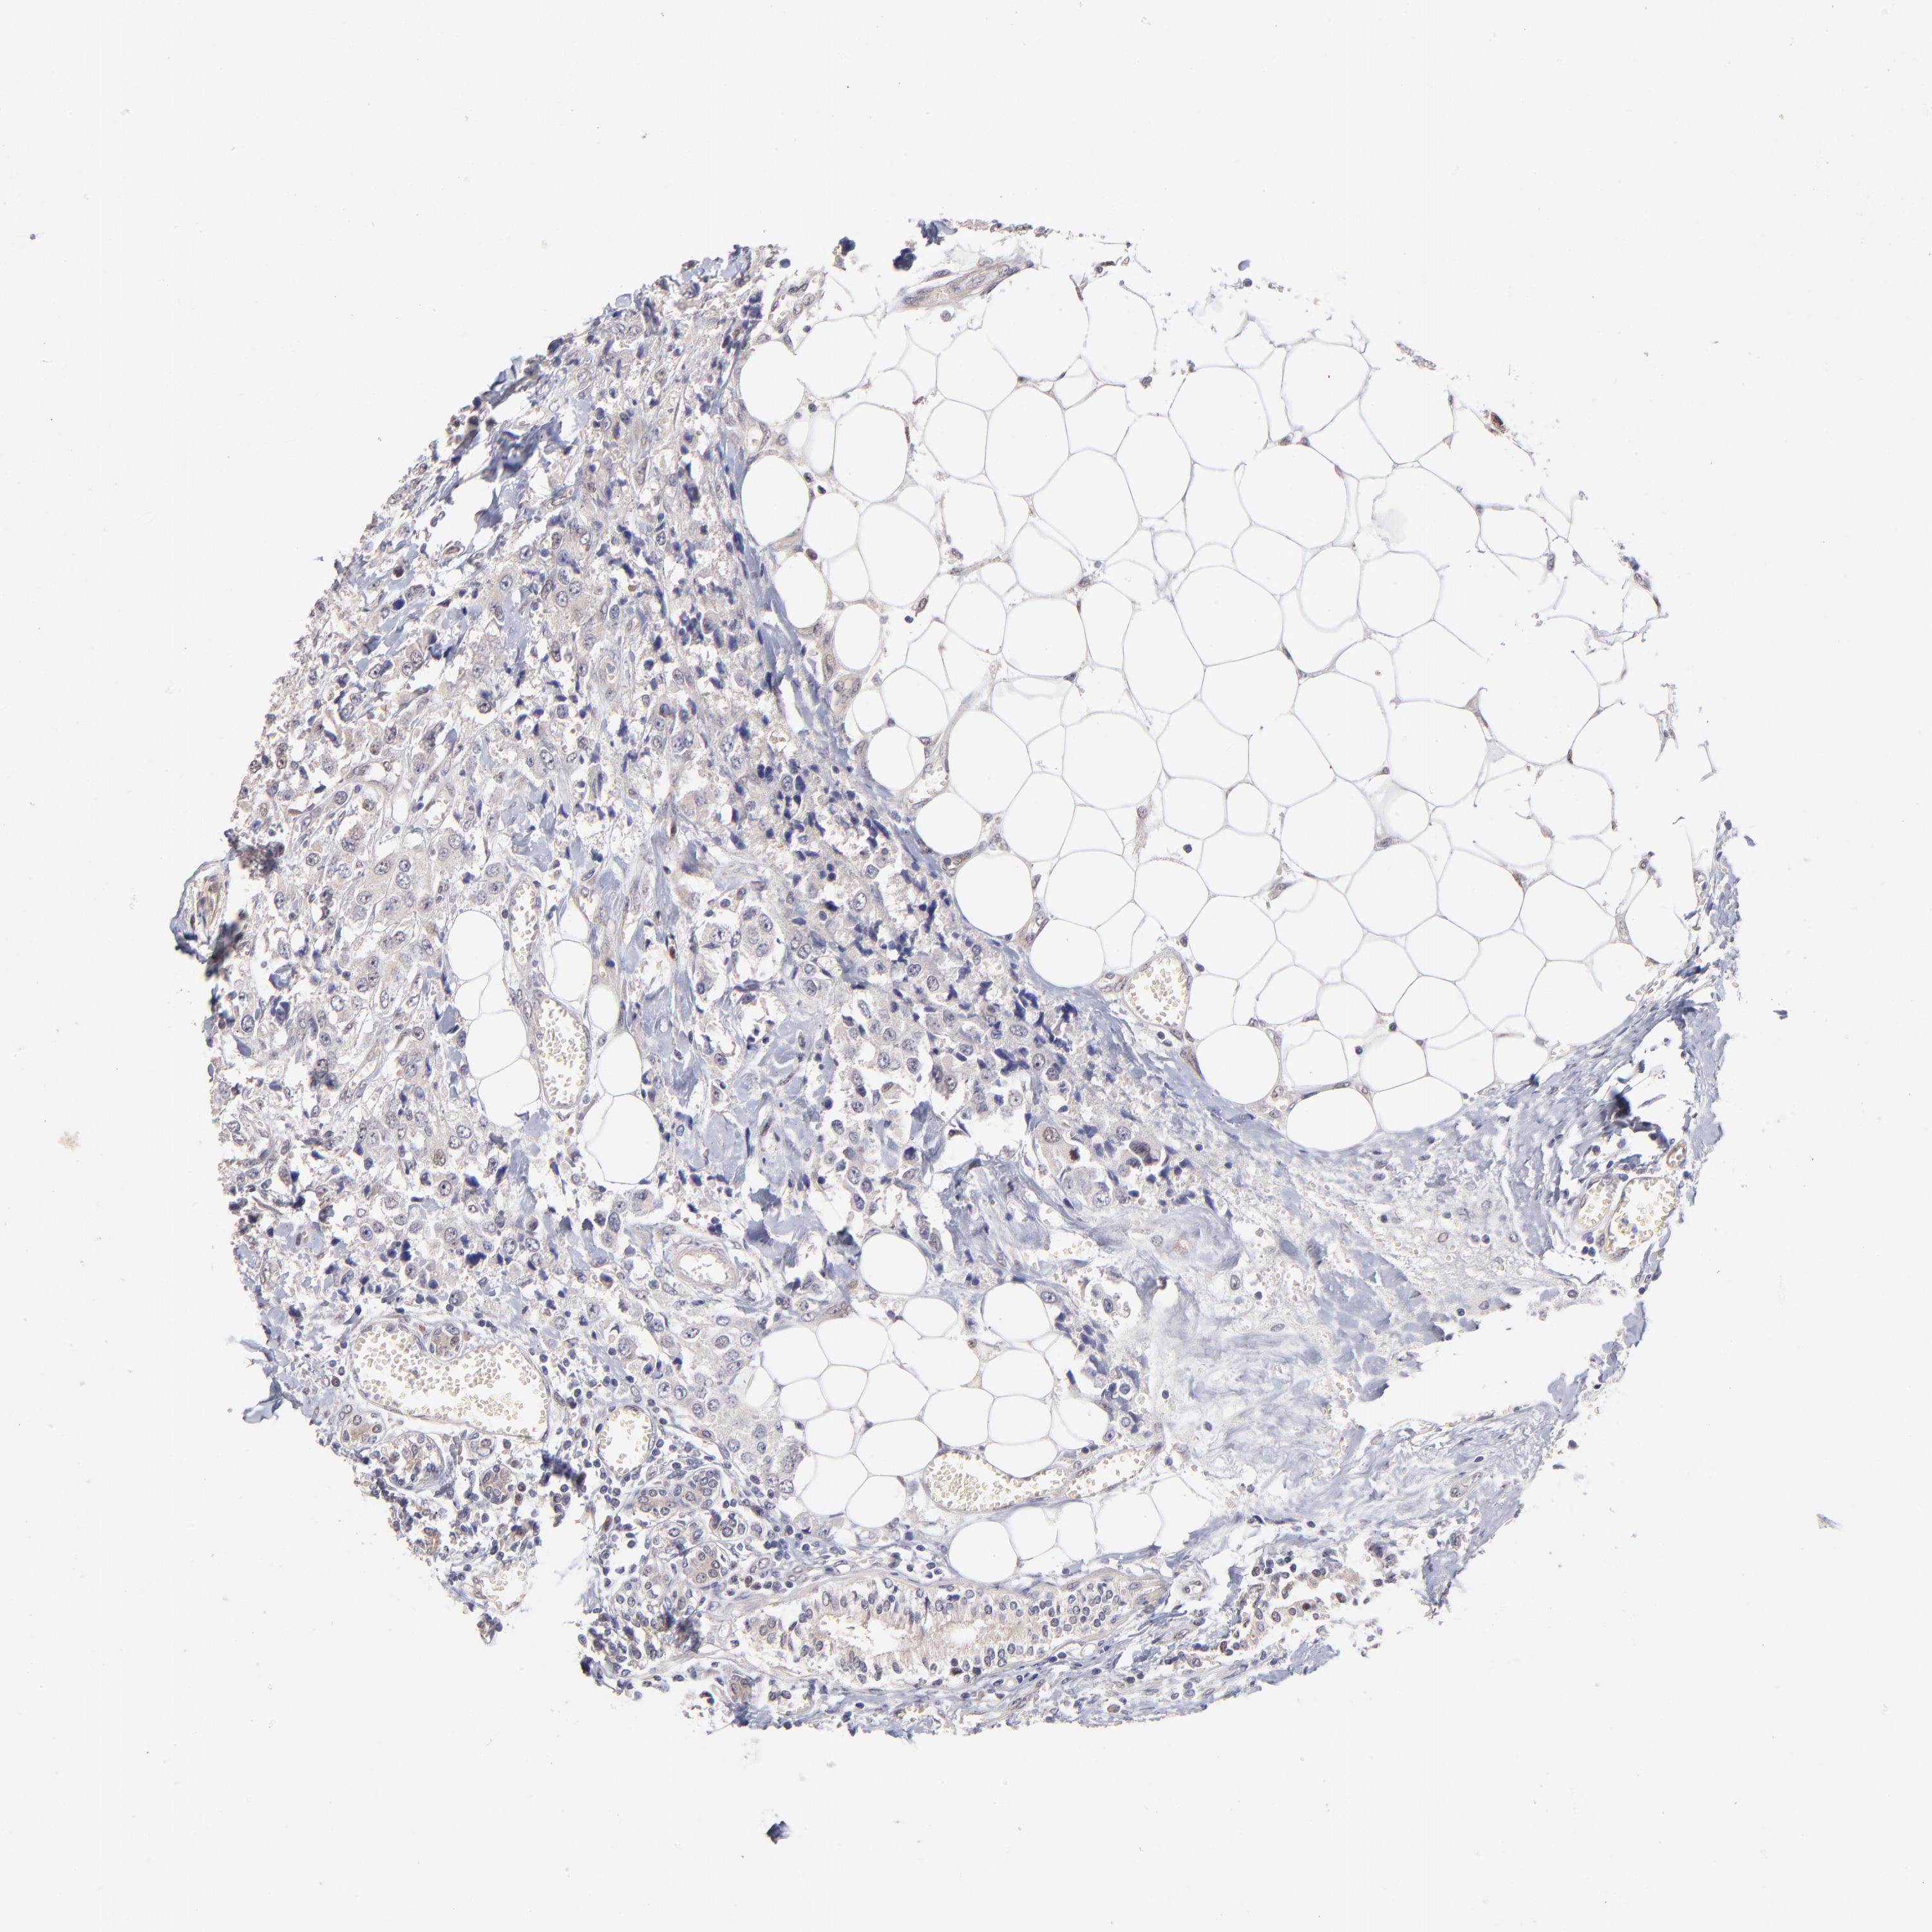

Breast cancer

Human cancer